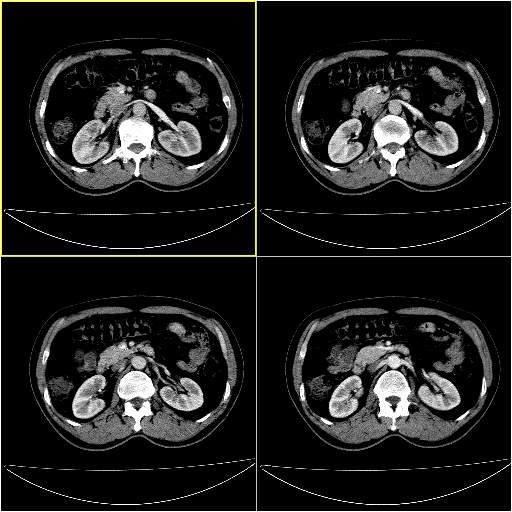

男性,54岁,皮肤黄染,搔痒一周余.b超示肝左叶回声异常.初步诊断1胆总管下段结石2胆囊结石伴慢性胆囊炎请各位战友帮忙看一下肝脏多发低密度如何解释恰当.增强效果不是很好.请大家见谅.

胆总管及肝内胆管扩张,考虑是结石!但,肝内的低密度区增强不明,可能是肝ca,因为肝ca在增强时呈快进快出.另年胆总管扩张原因,可以考虑一下是不是,胆管ca.再次要考虑肝内的低密度是否为海绵状血管瘤所致!

首先,胆总管下端结石梗阻伴肝内胆管扩张可确定。

其次,增强动脉期肝静脉显影,肝实质密度不均。——此为右心功能不全引起肝淤血的表现。

另外,肝八段低密度占位,呈多灶性,考虑肝脓肿或肝癌可能,(图像质量欠佳)建议进一步检查。

既然做了增强,为什么光提供延时期片子,肝动静脉期肝右叶前下段病灶增强如何?另外胆囊壁增厚,欠规整,内密度不均,与肝右叶病灶分界不清,增强表现怎样?肝内胆管轻度扩张,胆总管扩张,但未见明显结石影,也应提供增强早期图像才好鉴别扩张原因。片子较清,但不够完整,暂考虑1.胆囊癌肝局部浸润,或肝癌胆囊侵犯,2.胆总管下端或胰头钩突部占位。总之本人看不明白,请高手画图指示,先谢了!

由于胆囊窝内结构显示不清,肝脏病灶又邻近胆囊窝首先考虑胆囊癌肝受侵犯。而后因肝脏病灶强化有渐进改变,且相邻胆管扩张,故考虑肝胆管细胞癌待排。

左肝胆管细胞癌。

胆总管下端结石。